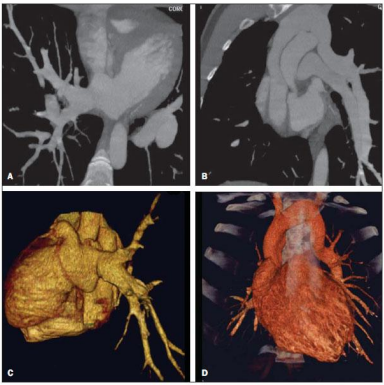

Considere a imagem para responder à questão.